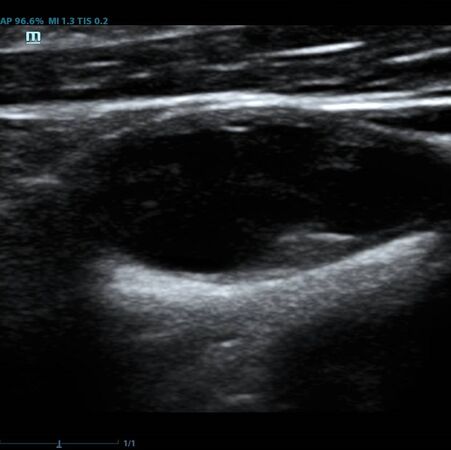

Помимо базовых целей по выявлению атеросклероза, бляшек, оценки кровотока и значимости стеноза, врачу ультразвуковой диагностики ставится и множество других задач при исследовании сонных артерий. Одна из них – оценка стабильности бляшки.

Ранее коллеги опирались на визуальную оценку, насколько бляшка гомогенная и какова её эхогенность. Есть ли в ней кальцинаты или анэхогенные участки. Для этого использовались международные классификации, с разделением среза бляшки по процентам – сколько гипер- и сколько гипоэхогенных зон. Такой метод  оценки до сих пор весьма популярен, однако он имеет минусы. Основной его минус в субъективности. Тяжело на глаз сказать, на 49,9% своей площади бляшка эхогенна или же на 50,1%, да и глаз у каждого человека несколько разный. Один специалист скажет – тут больше 50% гипоэхогенного, другой, что менее. Таким образом, метод сильно зависит от оператора – специалиста ультразвуковой диагностики.

Современное решение – компьютерный анализ структуры бляшки. Ультразвуковая система экспертного класса Mindray DC-8 способна провести программный анализ полученного изображения бляшки и дать количественную оценку её структуры. Для этого используется показатель GSM – Grey Scale Median. Прибор рассчитывает медиану по показателям серой шкалы в выделенной зоне и выдает данные в виде графика распределения эхогенности и числовых данных для количественной оценки. Таким образом, исследование становится более объективным и воспроизводимым, снижается зависимость от оператора (человеческого фактора).